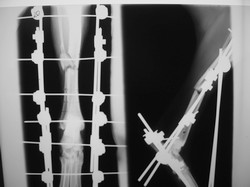

PRÁCTICAS CURSO DE FIJACIÓN EXTERNA PERFECCIONAMIENTO.

Artrodesis tarso.